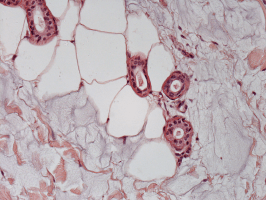

Spoločné histologické škvrny ukazujú výplň (svetlo modrá) dokonale integrovanou do spojivového tkanív s kolagénnymi vláknami, tukovými tkanivami a kanáliky potných žliaz. Neexistujú žiadne imunoreakce.